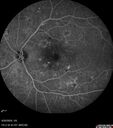

Severe NPDR

53 year old man with blurred vision (needs glasses).

Diabetic for 10 years with poor control

VA 20/32 OU